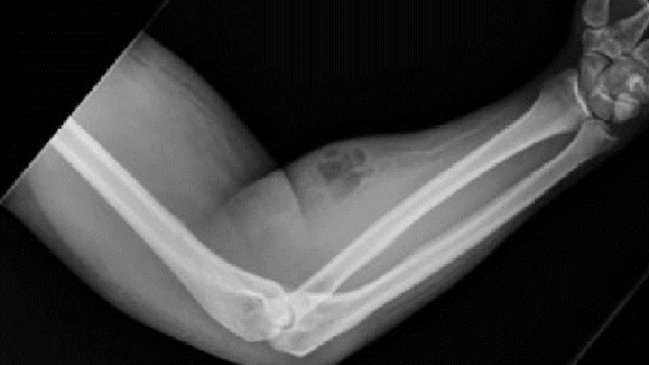

Su brazo estaba evidentemente inflamado, pues se inyectaba al menos una vez al mes durante los últimos 18 meses.

Un rarísimo caso quedó al descubierto gracias a la revista médica Irish Journal: El de un hombre de 33 años que solía inyectarse su propio semen en el brazo para tratar sus dolores crónicos en la espalda.